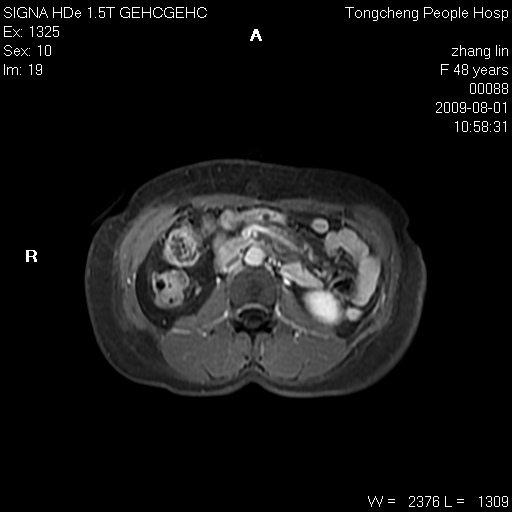

女,48岁。健康体检,彩超发现右肾占位性病变。平素健康。

临床诊断:右肾占位性病变,性质待定(囊肿?肿瘤?)。

上中腹部mr平扫+增强扫描,图像如下:

右肾上极见一类圆形病灶,t1wi呈等信号t2wi呈等高混杂信号,三期增强无强化,边界清---考虑囊肿出血。

同反相位均表现为等信号,病变无强化,考虑含蛋白的囊肿可能,弥散加权相或许有些帮助,

肝囊肿

慢性胆囊炎